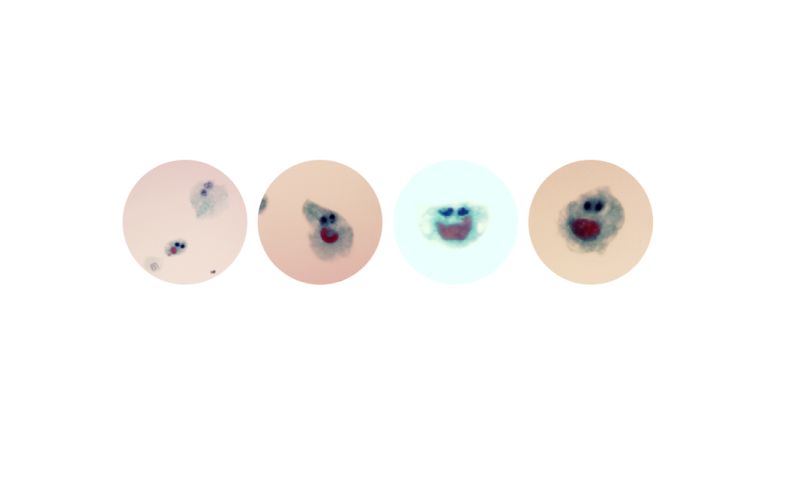

July 2023BAP1 loss in Mesothelioma

Leonie Wheeldon

Consultant Biomedical Scientist - Diagnostic Cytopathology Royal Cornwall Hospitals NHS Trust